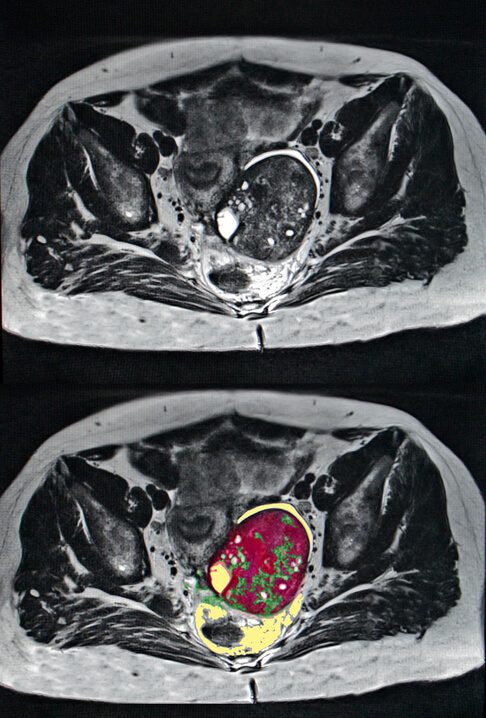

Ovarian cancer scan

Medical scan showing location of ovarian cancer